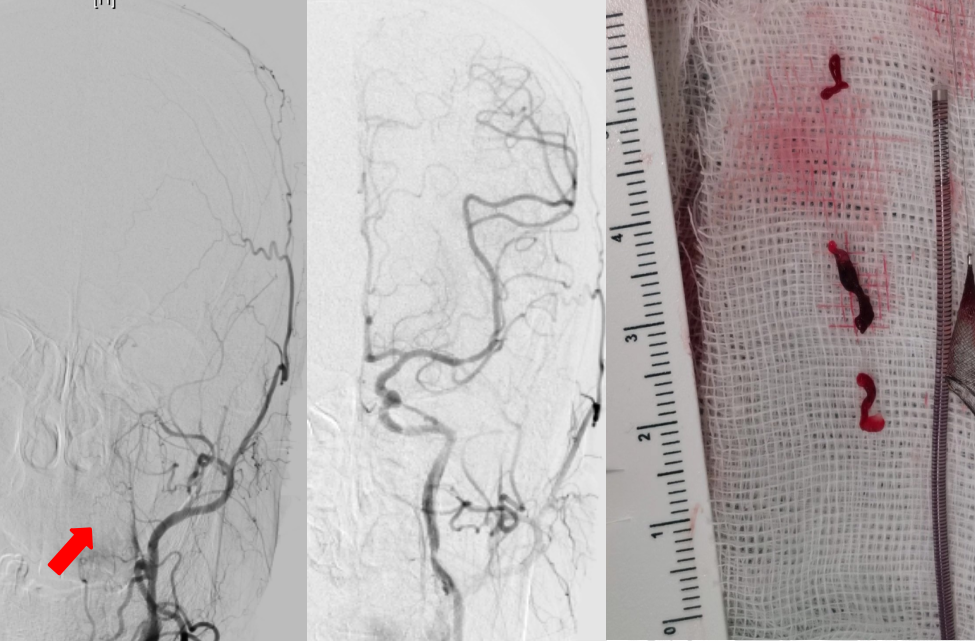

神经内科介入团队快速给予患者脑动脉造影,多名医师针对闭塞血管病变特点,通过脑血管介入和机械再通技术(以下简称“取栓”技术)为患者进行血流再通,术中完成取栓后,患者的言语以及右面部、右半侧肢活动立即恢复活动能力,3天后恢复至完全正常,可以独立行走出院。

图中红色箭头所指为闭塞的左侧颈内动脉,对比术前及术后再通的颈内动脉影像病人的血管完全再通,可见取出的大量暗红色的血栓